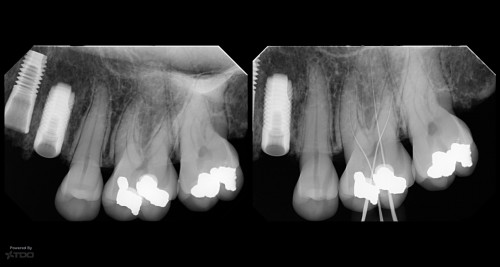

16 yr recall

By Gary Carr / July 10, 2018